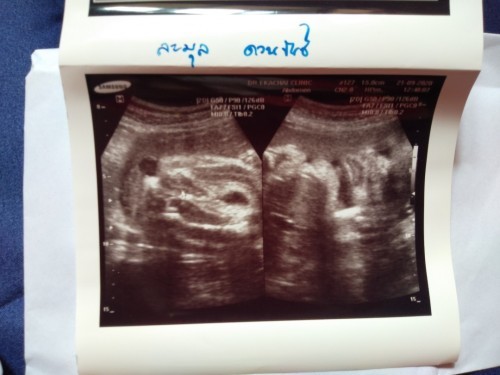

มาอวดรูปตอนซาวด์กันหน่อยค่ะ แม่ๆกำหนดคลอดเดือนไหนบ้างคะ